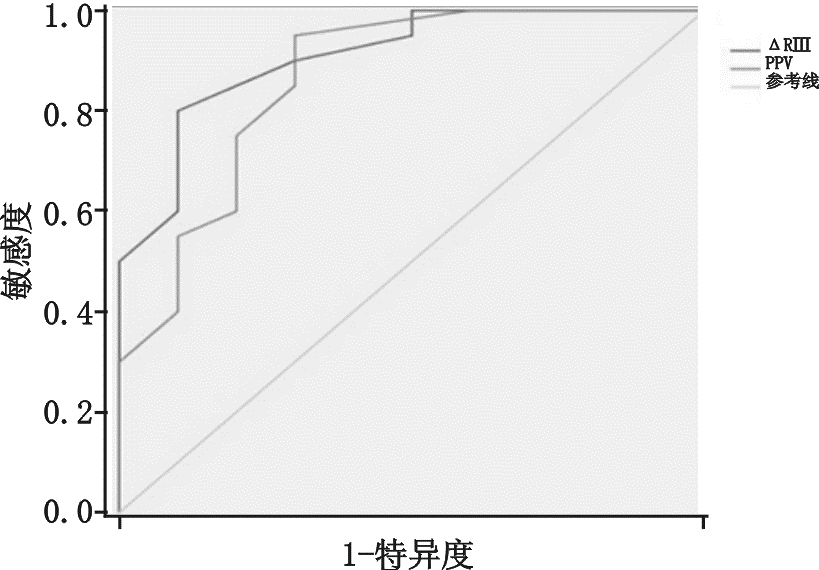

通过受试者工作特征(ROC)曲线评估ΔRⅡ与PPV预测SVV≥12%能力(见图 5),其曲线下面积(AUC)分别为0.910±0.055与0.865±0.076,两者比较差异无统计学意义。以ΔRⅡ临界值为11.5%预测SVV≥12%,其敏感度80%,特异度90%;

| 图 5 受试者工作特征曲线评估ΔRⅡ与PPV预测SVV≥12%能力 |

机械通气患者,吸气相胸腔内正压增大,导致右心回流减少,同时右心后负荷增加,致右心每搏量减少,经过两三个心动周期后左心室的前负荷减少,就这样左心室的每搏量随着呼吸周期波动,在吸气末每搏量达最大值,呼气末每搏量为最小值,这种现象在心脏Staring 曲线的上升支更明显,在平坦支就不明显,所以这种变异是反应心脏前负荷的指标[4, 13]。心电图R波幅度随呼吸周期性变化的理论基础是“Brody 效应”[7],即心脏内血液的电阻比心肌组织低,心脏内血液越多电阻越小,传导至身体皮肤表面的电量越大。基于心肺交互原理,机械通气吸气相正压通气挤压肺血管床使左室前负荷增加,左室容积增加,故在吸气末左室前负荷最大即左室容量最大,此时R波波幅最大,每搏量也最大,而呼气末R波波幅最小,每搏量也最小。实际上R波波幅从原理上代表的是心室内的血容量,每搏量是代表着从心室射到主动脉的血容量,两者是同源的,所以心电图呼吸周期性R波波幅变化与每搏量变异相关,且能反应血管内容量。研究表明V5、V6的R波受左室在胸腔内位置影响较大,而Ⅱ、Ⅲ、AVF导联R波基本不受影响[14, 15],故本研究选择ΔRⅡ、ΔR Ⅲ、ΔR AVF为研究对象,结果显示ΔRⅡ、ΔR Ⅲ、ΔR AVF与SVV相关,而且我们发现ΔRⅡ与SVV相关性最好,明显优于ΔR Ⅲ、ΔR AVF,与先前研究结果一致[14],这可能与Ⅱ 导联与正常心脏电轴最接近的原因相关。大量研究表明SVV ≥12%为预测容量反应性的阈值[5],本研究比较SVV≥12%组与SVV < 12%组的HR、CVP 、MAP、CI,均显示差异无统计学意义,但全心舒张末期容积指数(GEDVI)两组间差异具有统计学意义,说明预测容量方面GEDVI优于HR、CVP 、MAP、CI,但其监测需行PICCO,费用昂贵,且操作不便。笔者通过受试者工作特征(ROC)曲线评估ΔRⅡ预测SVV≥12%能力,其曲线下面积(AUC)为0.910±0.055(P<0.01),与PPV预测SVV差异无统计学意义。以ΔRⅡ临界值为11.5%预测SVV≥12%,其敏感度80%,特异度90%,说明在感染性休克机械通气的患者ΔRⅡ能准确反应或预测SVV值,虽然本实验未行容量负荷试验,但这给我们启示是否ΔRⅡ可作为SVV替代指标应用于机械通气患者辅助评估容量反应性,待进一步研究证明,进而开发应用ΔRⅡ这个新指标在心电监护仪上持续监测,如同PPV一样。

总之,机械通气的感染性休克患者,呼吸周期性ΔRⅡ与SVV有显著的相关性,可以准确预测SVV≥12%,可能ΔRⅡ如同PPV一样可以替代SVV准确预测容量反应性。由于本研究样本量不大,ΔR测量有误差,R波波幅改变的因素还有很多,比如心包积液[16],心肌缺血[17],QRS波电轴改变[18],心肌纤维本身的传导性[19]等,ΔRⅡ是否能直接评估患者容量反应性尚需进一步研究,进而为我们带来一个全新的动态血流动力学指标。